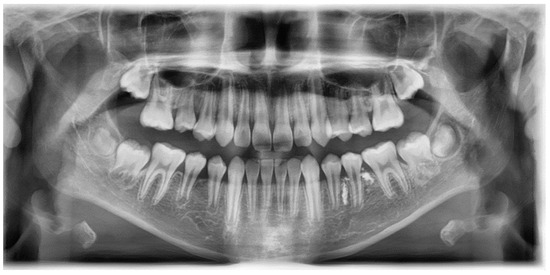

Figure 2.

Eleven months after tooth extraction. Panoramic radiograph. The underdevelopment of the left mandibular second premolar tooth germ (red arrow) was observed compared with the opposite one (blue arrow).

A band and loop space maintainer was delivered after the eruption of the left mandibular first molar. Three years after the extraction, the development of the successive permanent tooth was observed (Figure 1d). Four years post-extraction, the successive tooth was in the pre-eruptive phase, with continuous growth and pre-eruptive movement in the alveolar bone, similar to those in the opposite tooth (Figure 3).

Figure 3.

Four years after tooth extraction. Panoramic radiograph. Development of successive permanent tooth was observed (pre-eruptive phase).